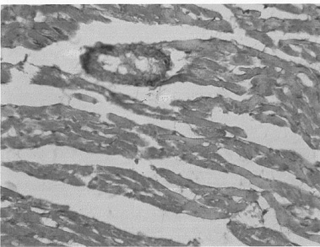

При гистологическом и гистохимическом исследовании миокарда крыс опытной группы были выявлены структурно-функциональные изменения карди- омиоцитов проводящей системы, что свидетельствует об ответной реакции миокарда экспериментальных животных на воздействие одночасовым раздавливанием. В проводящих кардиомиоцитах выявляются признаки белковой дистрофии, что подтверждается потерей клетками нормальной поперечной исчерченности и ее заменой в основном бледно-зернистыми образованиями. Наиболее часто зернистость располагается по соседству с ядром или околоядерной вакуоли. Ядра при этом несколько увеличены. Зернистость распространяется по всей ширине мышечных волокон, и в связи с развивающимся отеком, волокна становятся набухшими, расширенными.

Рис.1. Гомогенизация мышечных волокон

Межклеточная рыхлая соединительная ткань отечна и при окраске по Ван-Гизону приобретает желтоватый оттенок. На срезах, окрашенных методом Селье, выявляются очаги «фуксинофильной дистрофии» миокарда. Метод использован для выявления ранних морфо-функциональных сдвигов со стороны миокарда. «Фуксинофильная дистрофия» выявляется не только при нарушении кортикостероидного и электролитного обменов, но и при других патологических состояниях. Через 24 часа после декомпрессии местами выявляются грубые изменения проводящих кардиомиоцитов. Отдельные мышечные волокна, где гомогенизация распространяется и на саркоплазму, представлены в виде гиалиноподобных обра-зований.